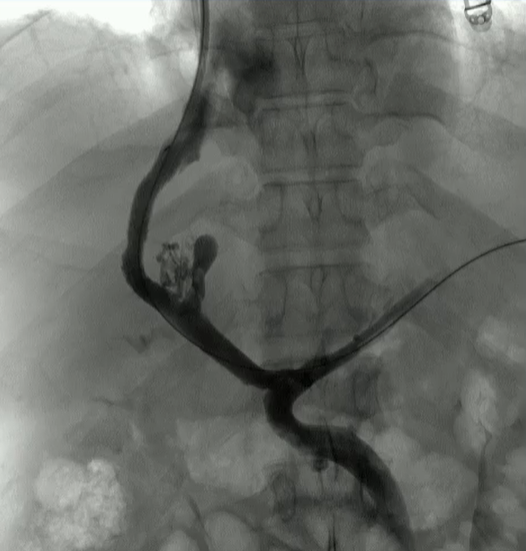

该程序包含以下步骤: 经脾脏入路:在超声引导下,刺穿脾静脉内的一个实质内分支。 在通过脾静脉造影确认了静脉通路后,导管和导丝被推进,以穿过脾静脉并抵达血栓化的门静脉。在门静脉/右门静脉分支处放置圈套器,为TIPS穿刺精准定位。TIPS穿刺圈套器,并穿过圈套器完成TIPS

步骤: 鉴于慢性血栓形成的复杂性: 一种经脾脏途径的门静脉再通术(PVR)。 随后是经颈静脉肝内门体分流术 。

结果:术后影像学检查显示门静脉和脾静脉的血流情况有所改善,且残留血栓极少。